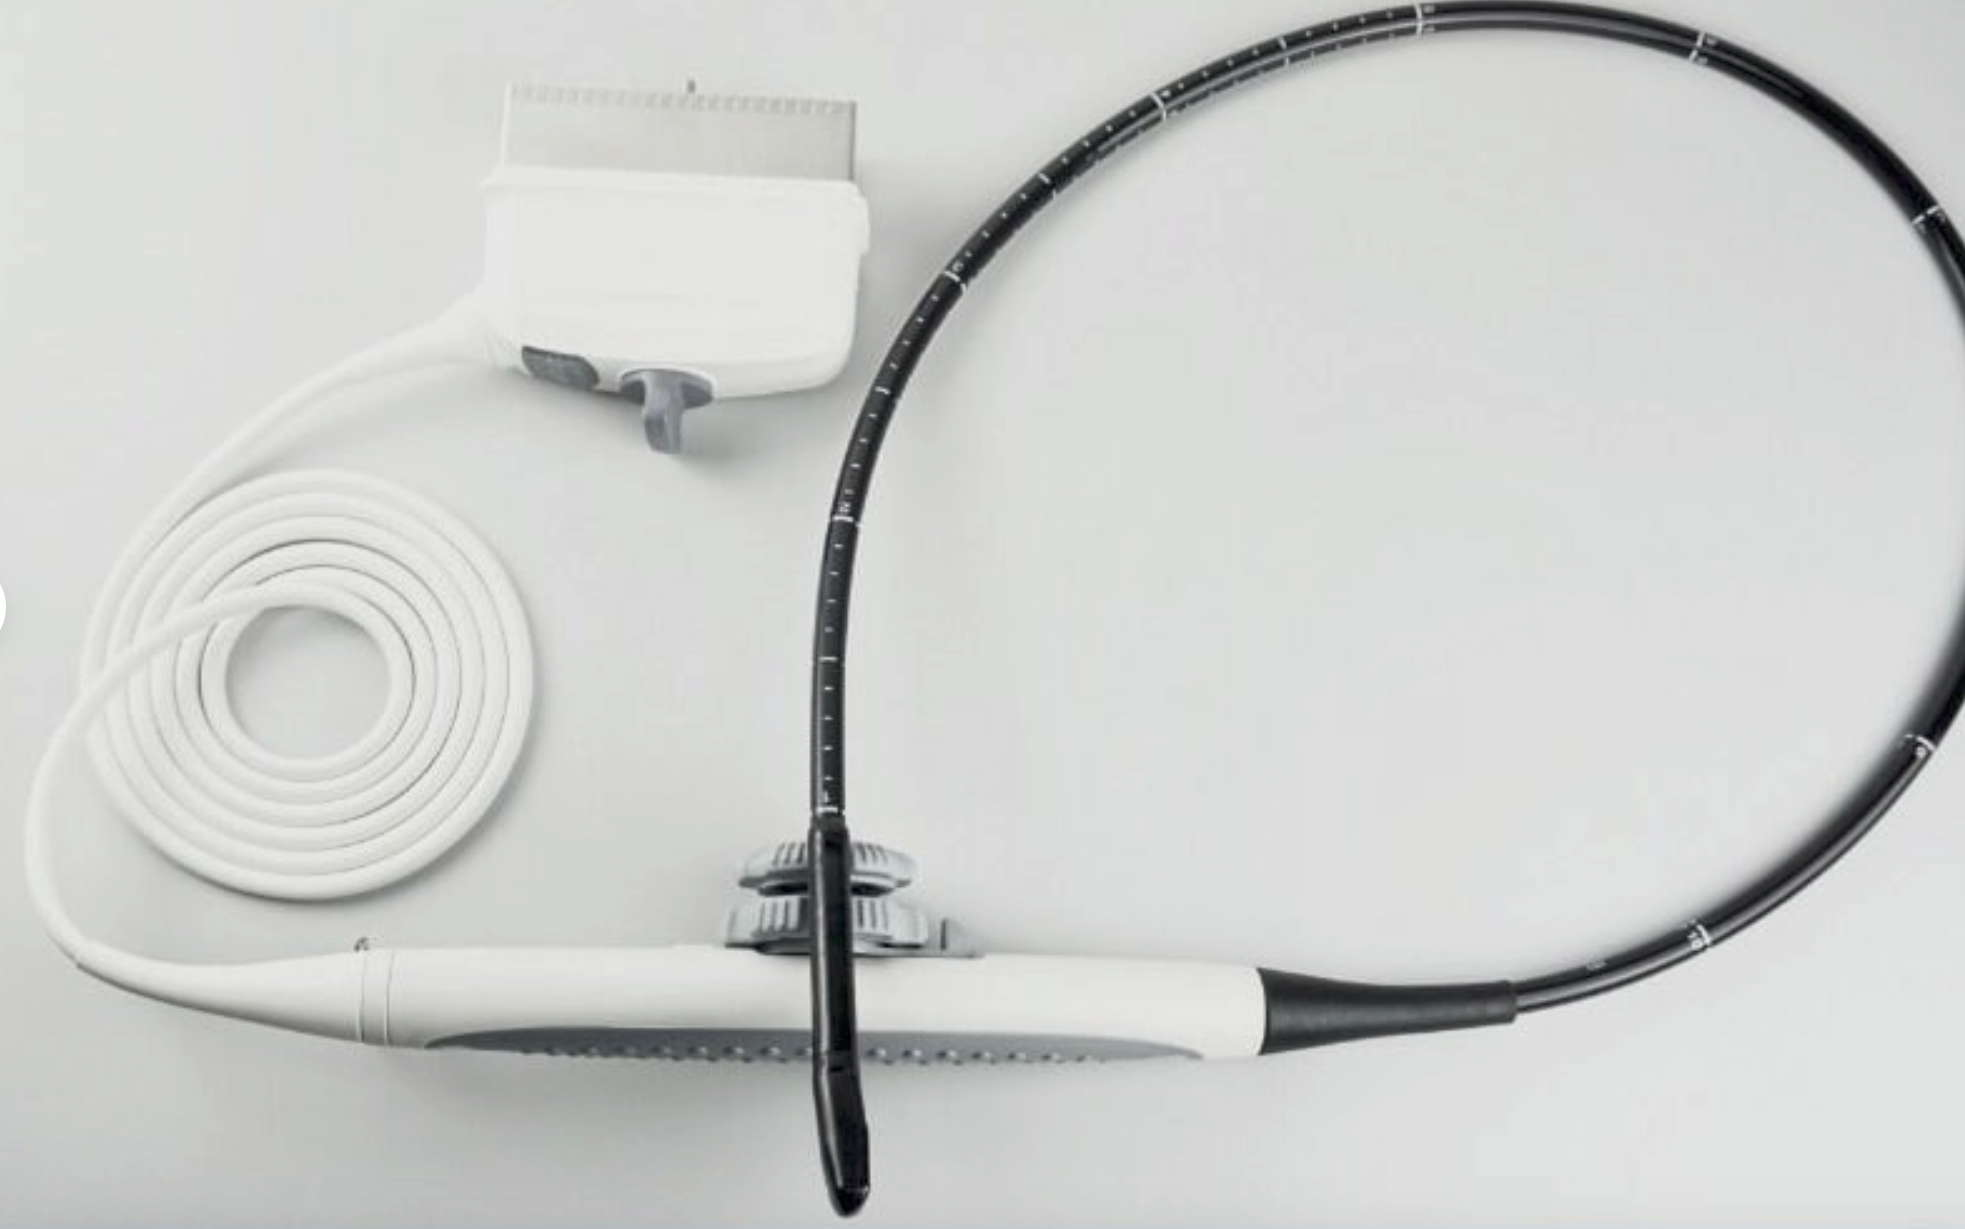

Probe Function: 3.5MHZ convex, abdominal organs

Probe 2: 7.5MHZ Transvaginal probe:gynecologic examination

The Ultrasound Scanner is a state-of-the-art device designed for comprehensive pregnancy imaging. It features both convex and transvaginal probes, allowing healthcare professionals to obtain detailed images of the fetus and surrounding structures. This dual-probe system enhances diagnostic accuracy, making it easier to monitor the health of the unborn child. Expecting mothers benefit from these advanced imaging techniques, enabling early detection of potential complications.